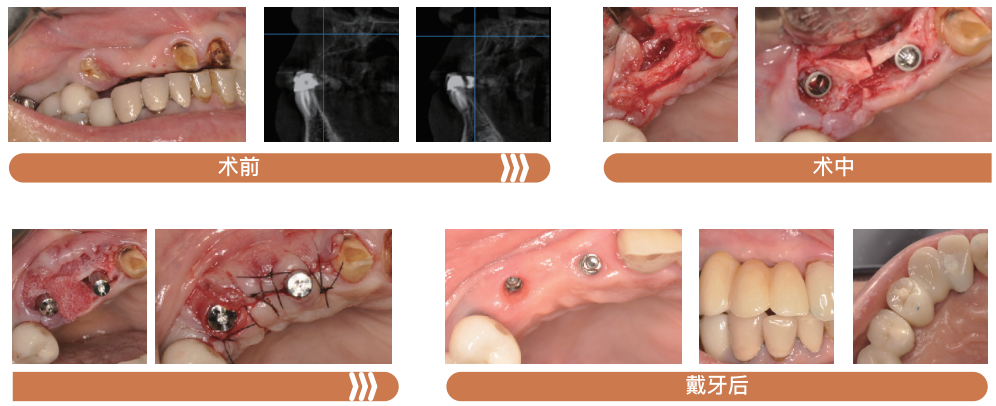

实验显示,诚谷快口腔用骨填充材料可快速诱导缺损区血管生成,促进血供重建,独特的材料特性和结构设计赋予了其强大的引导成骨功能,到24周软硬组织均未有明显分界,且完全转化为自身骨组织,表明其具有很高成骨转化率。

诚谷快口腔用骨填充材料临床应用案例